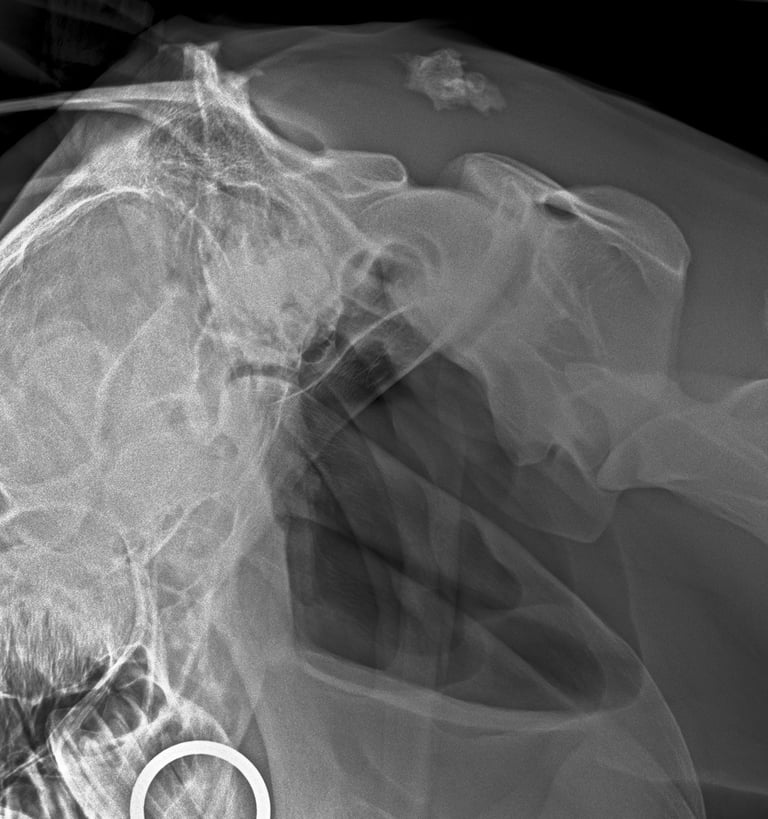

DIAGNOSTICO POR IMAGENES: ECOGRAFIA Y RADIOGRAFIA